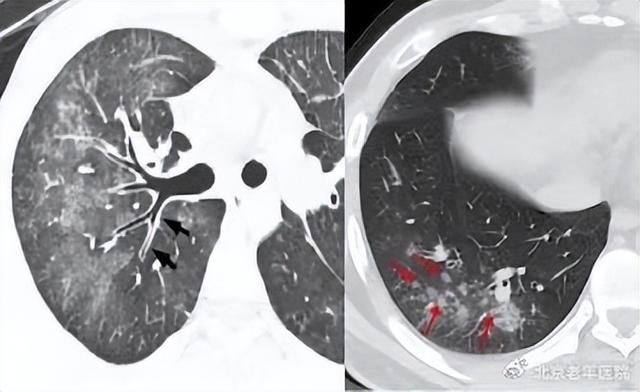

支原体肺炎在影像学上也有一些特征性的表现:

1)肺部出现低密度、边缘模糊、呈云雾状分布的阴影,通常被称为磨玻璃状阴影。

2)当肺实质受累时,可能出现大片实变阴影,部分病灶还可能有小的空洞。

3)在CT影像上,可以看到间质性浸润呈结节状或网状的阴影,这些阴影呈截断性分布。

4)病灶周围的支气管壁变厚,支气管血管增粗,晚期还可能出现支气管扩张。

5)肺门淋巴结可能会增大,胸腔积液也可能出现。

以上是支原体肺炎的诊断方法和影像学表现的简要说明,通过这些方法可以更好地诊断和了解支原体肺炎的状况。